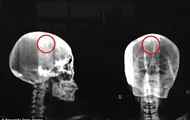

Китаянка 46 лет прожила с 4,5-сантиметровой иглой в мозгу Дата (9/10/2015 6:48:00 PM +03:00)

Женщина по фамилии Лю жаловалась на частые головные боли, однако истинную

причину их

возникновения установили только после КТ.